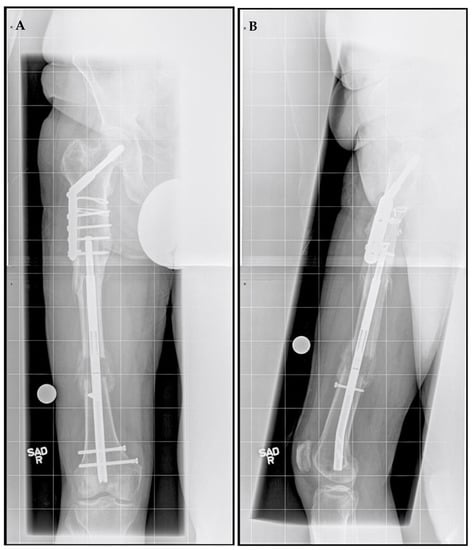

A right femoral osteoplasty was performed and a Precice MILN was inserted using the methods described above (Figure 2). The patient began lengthening as instructed on postoperative day five. He attended physical therapy and took vitamin D and calcium supplementation, as well as oxycodone as needed for pain management. Initial ROM of the knee joint was restricted from 0–50°, but full range was regained two months after surgery. He finished distraction 46 days after surgery (Figure 3). The patient completed consolidation 152 days after surgery and experienced no complications. At his latest follow-up appointment, his long leg films (Figure 4) demonstrated complete healing, remodeling, and equal limb length. The patient has returned to his active lifestyle, including skiing, and reported that he felt better on his bike and skis.

Figure 3.

Post-traumatic femoral lengthening in a 71-year-old male patient after the distraction phase. (A) Antero-posterior and (B) lateral of the right femur after the completion of 3 cm distraction with Precice MILN. Gray dots on the bottom represent X-ray calibration spheres.